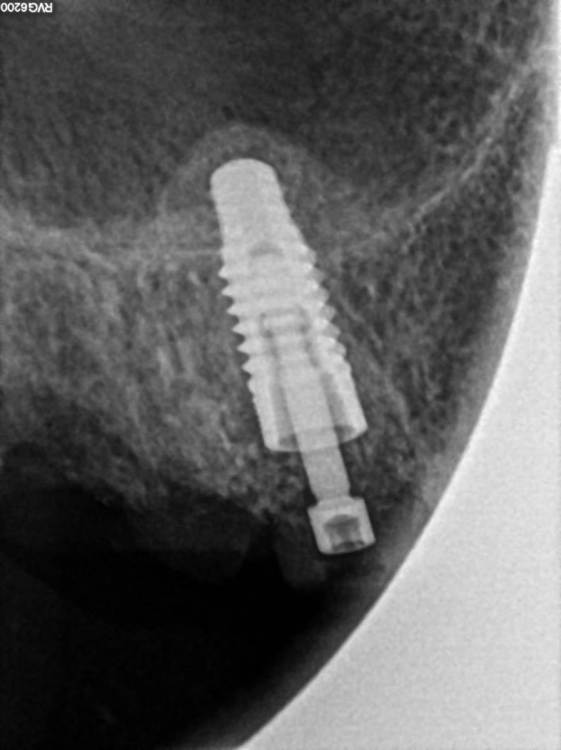

Korabahtoff Опубликовано 6 декабря, 2022 Поделиться Опубликовано 6 декабря, 2022 Хеликс? Какой диаметр? Отличная работа!? 1 Ссылка на комментарий

TIGER Опубликовано 7 декабря, 2022 Автор Поделиться Опубликовано 7 декабря, 2022 @АнтонТЛТ @Irouil Друзья ПЕРИОтест от слова ПЕРИОдонт?у импланта нет его,и замерять им не совсем корректно,у импланта совсем другие принципы @Korabahtoff спасибо !тут TITAMAX 4.0 Ссылка на комментарий